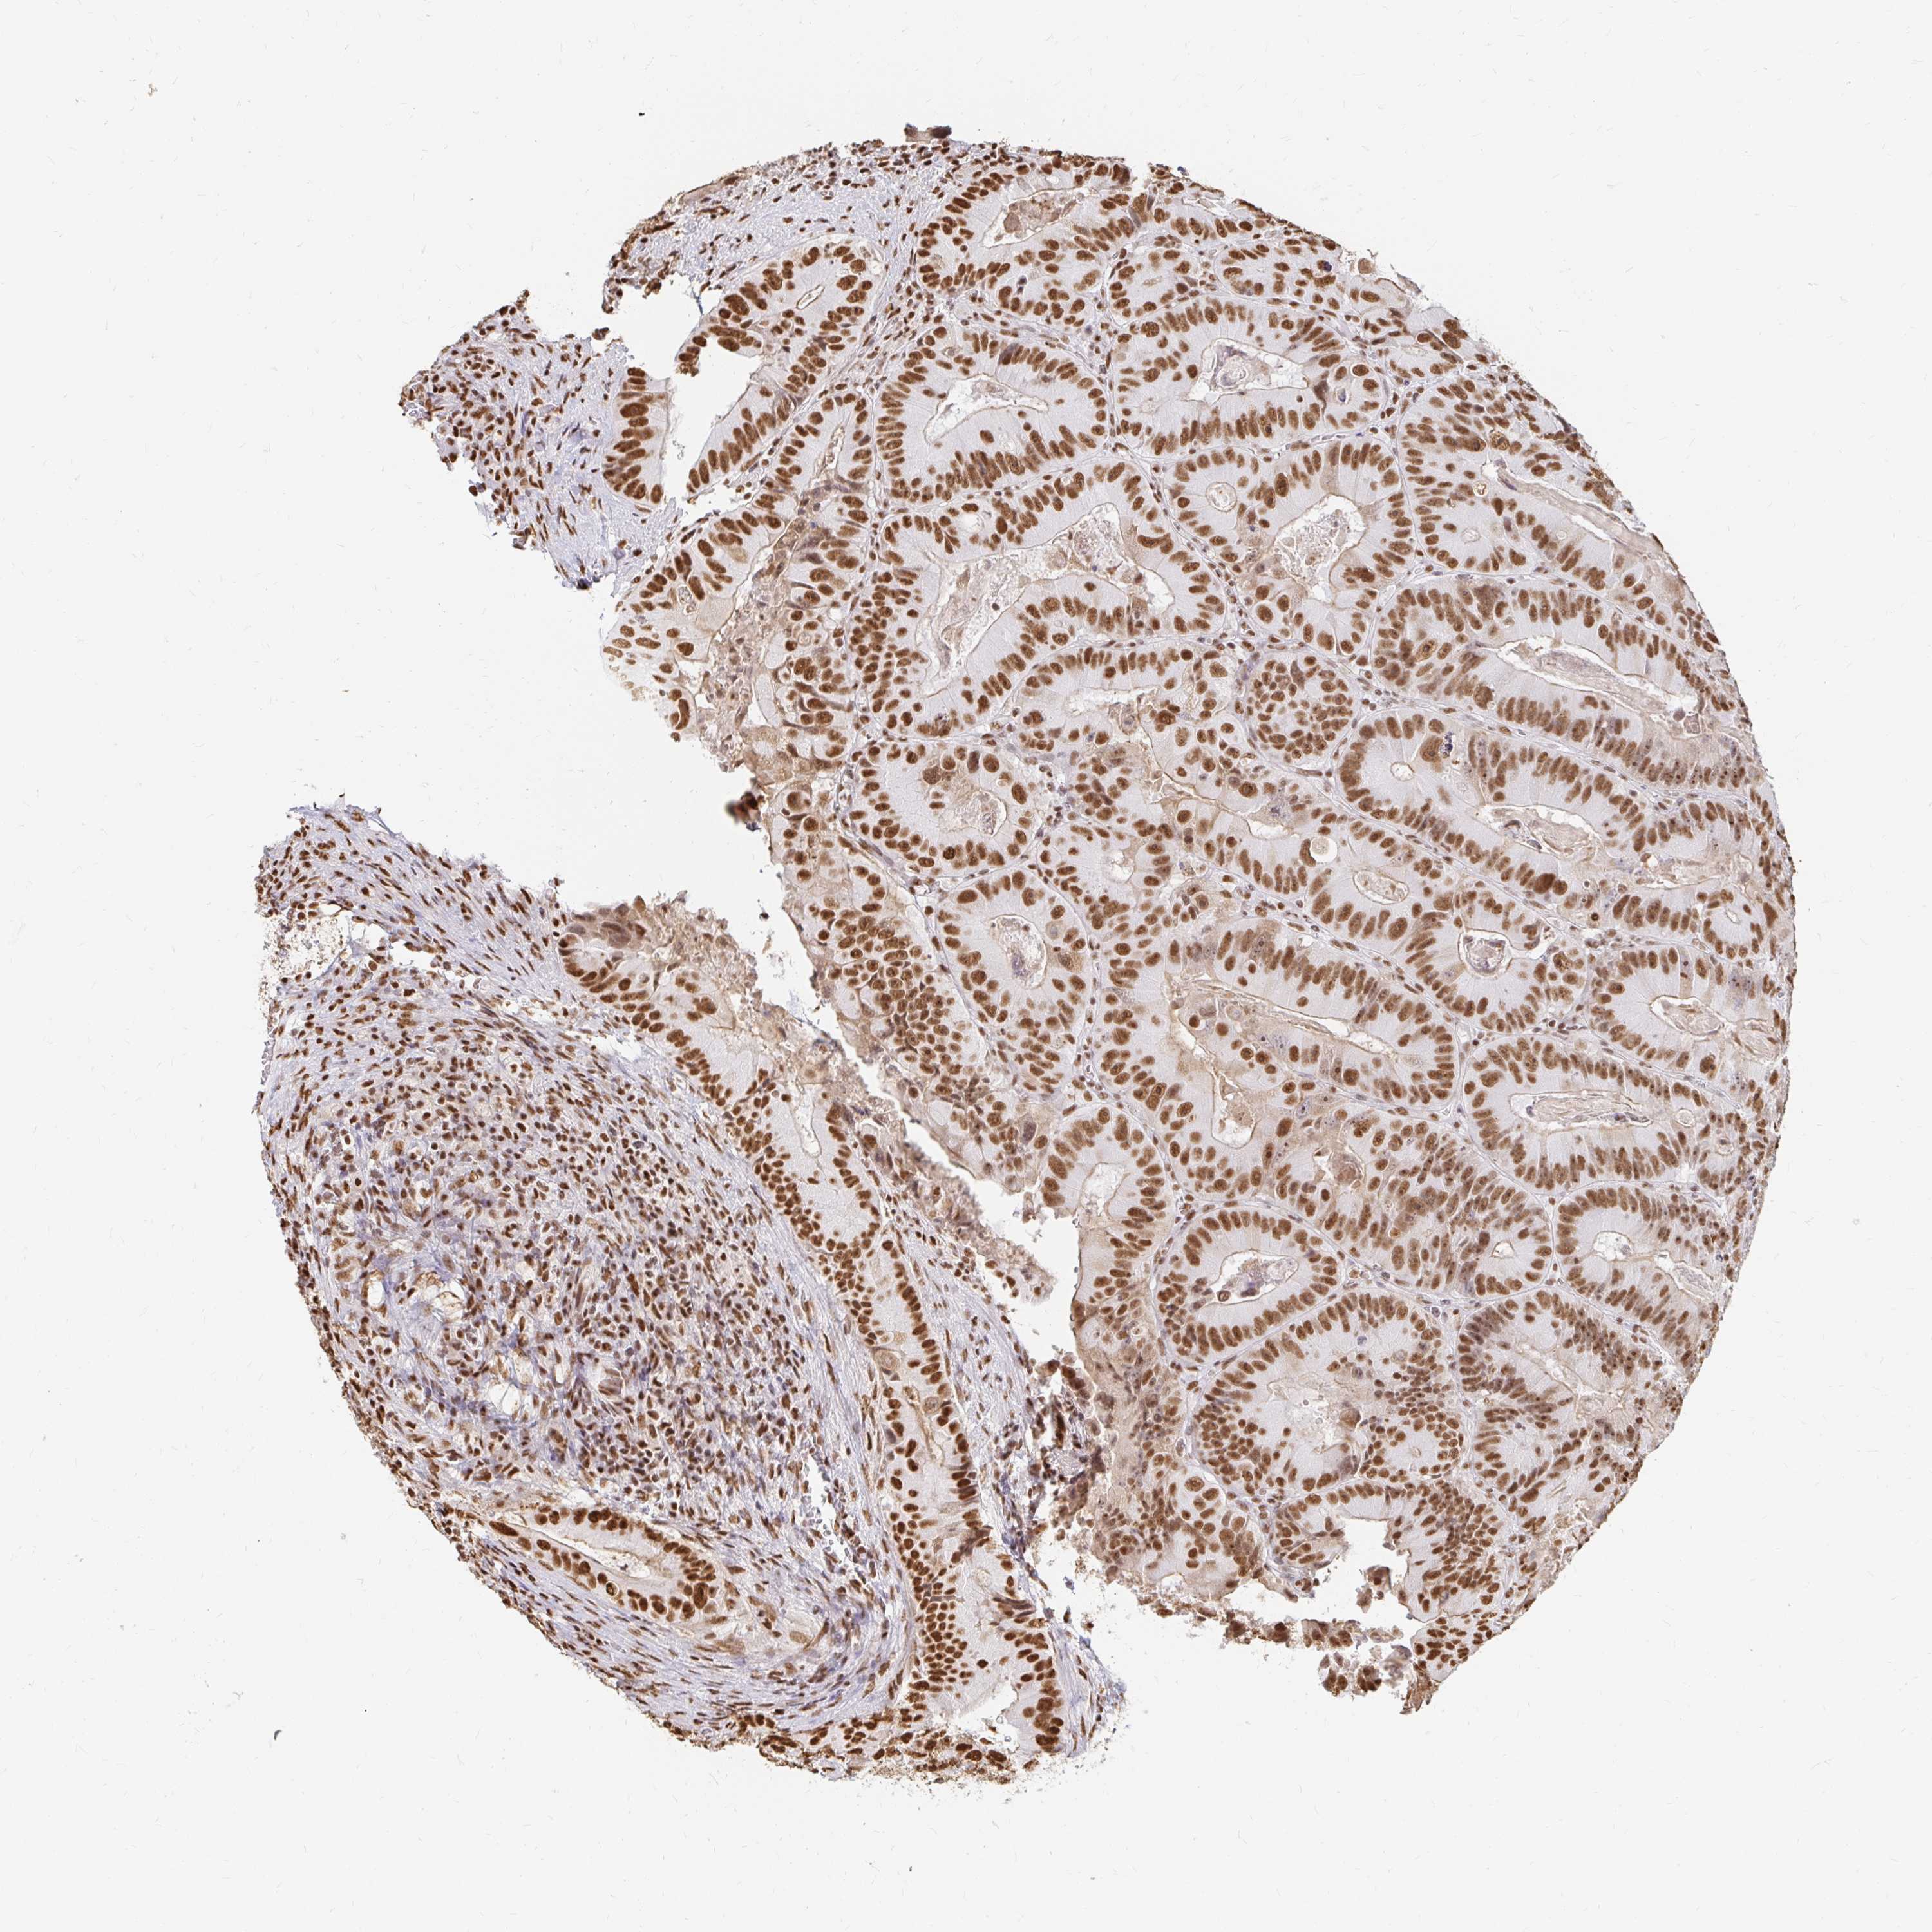

HNRNPU

CANCER COLORECTAL CANCER Show tissue menu

Colorectal cancer

Human cancer

Colon adenocarcinoma